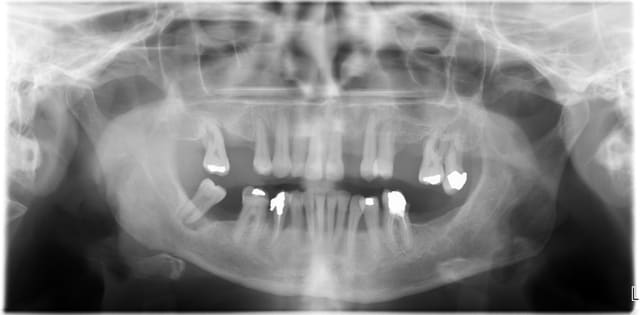

Noah, comment, sans examen clinique, peux tu évaluer la viabilité des dents montrées sur ces reconstructions 3D?

une simple radio te semble fiable aussi?

tu nous as habitué à plus de rigueur!!!

regardes cette radio panoramique par exemple...

petit indice, le "bientôt mci", à ton avis, il reste quoi actuellement (j'ai fait du "ménage")

Bientot mci f87uuw - Eugenol

Il est inutile de te rappeler que la perte d'attache parodontale ne peut être supérieure à la perte osseuse. Or sur le cas de Posit la perte osseuse, qui est très globalement de profil horizontal, ne semble pas excéder les 2/3 de la longueur radiculaire. De plus les quelques lésions infraosseuses présentent ne me semble pas ingérables par ttt parodontal adapté.

La seule interrogation concerne les lésions endodontiques éventuelles mais dans tous les cas si il y en a, elles n'ont pas "soufflé" les corticales.

Donc je réitère ma remarque et trouve que le choix d'extraction dans un tel cas est excessif.

En ce qui concerne la mobilité dentaire, elle est loin d'être étonnante vu le manque de calage postérieur et n'est en aucun cas un critère extractionnel.

Les cas présentés par Posit sont dans la majeure partie des patients atteint de parodontite. Extraire une dent ne permettra jamais de soigner le patient. Le problème n'est pas la dent mais la prédisponibilité du patient à la maladie parodontale.

Compte tenu du risque élevé qu'on ces patients de développer une péri-implantite et de la difficulté à traiter ce genre de maladie périimplantaire, je ne serais que hautement encourager les praticiens à essayer de conserver au maximum les dents de leurs patients.